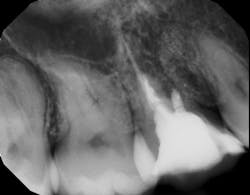

There is sufficient bone support around the remaining roots (at least 50% or more is needed) along with sufficient coronal tooth structure (figure 3).How does root amputation compare with other surgical procedures?

The prognosis is good for molar teeth treated with root amputation, provided case selection and treatment are performed properly. Fugazzottoreported 15-year cumulative success rates comparing molar root resection to molar implant placement, with survival rates of 96.8% for root-resected molars and 97.0% for molar implants.10 This study was done in private practice with proper oversight and case selection.Conclusion

Root amputation remains a viable treatment to save maxillary molars and can have long-term success rates equal to dental implant therapy (figures 9 and 10).Editor’s note: This article originally appeared in Perio-Implant Advisory, a chairside resource for dentists and hygienists that focuses on periodontal- and implant-related issues. Read more articles and subscribe to the newsletter.